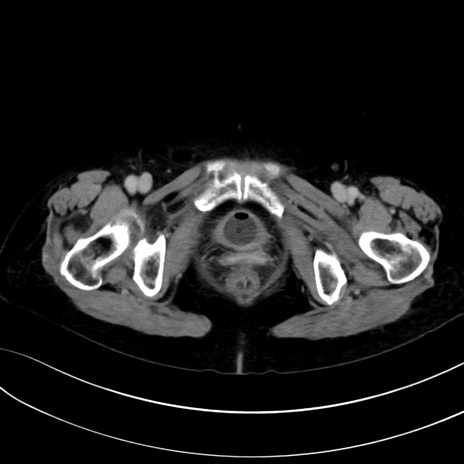

症例13 CT(横断像)1日半後